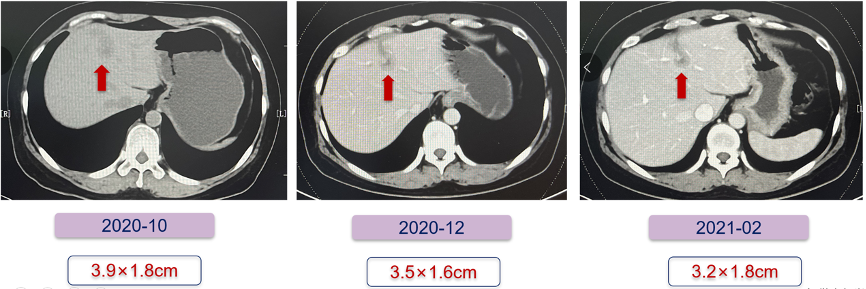

患者内分泌治疗的无进展生存期(PFS)为27个月,中间有8个月联合CDK4/6抑制剂治疗,肝内病灶缩小明显。建议患者再次使用CDK4/6抑制剂,内分泌药物换成芳香化酶抑制剂(AI),患者因经济原因拒绝。给予白蛋白紫杉醇(200 mg d1、8)化疗6周期,期间每2周期复查一次。CT提示复查肝转移较前缩小,疗效评价为稳定(SD)(图6)。

图6.患者化疗期间肝转移最大病灶变化情况